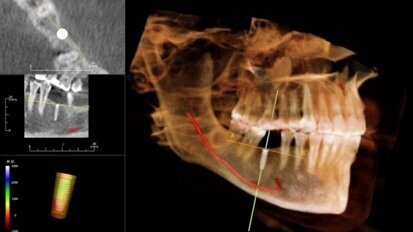

Cyfrowe narzędzia na różnych etapach leczenia implatoprotetycznego bezzębnej żuchwy

Użytkowanie protez ruchomych w żuchwie często stwarza pacjentom duży dyskomfort. Praca przedstawia częściową realizację kompleksowego planu leczenia...